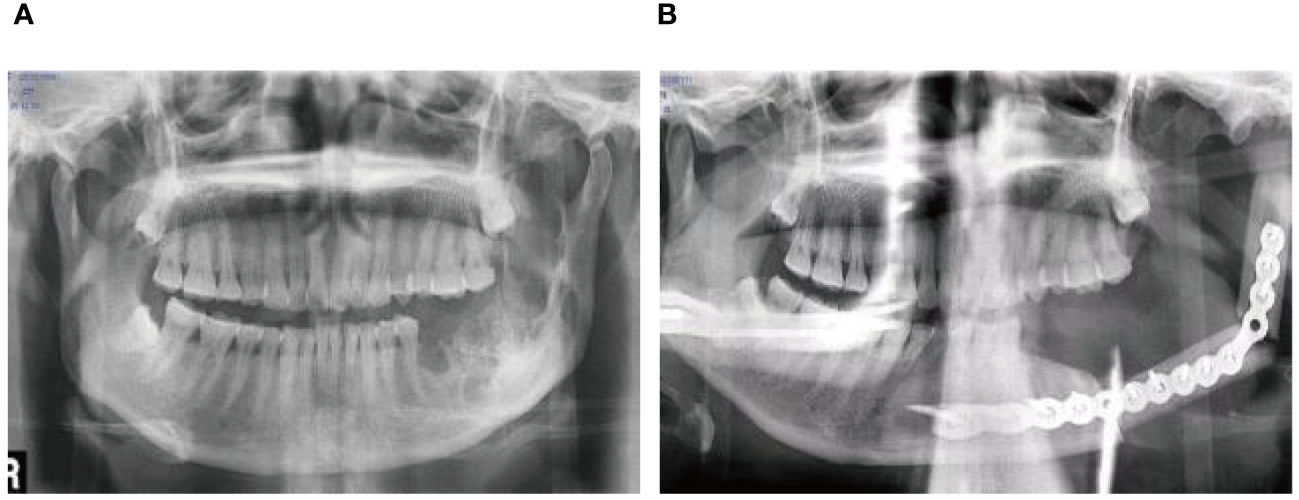

A 56-year-old female underwent surgery for ameloblastoma in the left mandible 2 years previously. Specialist examination revealed that the patient had swelling on the left face and neoplasm in the area surrounding the left mandibular angle and ramus, approximately 5.0 × 4.0 cm measuring in size. The patient also had a mild limitation in mouth opening, and 36, 37, and 38 were not detected in the oral cavity. According to the patient’s previous medical records and consultation report from the pathology department of our hospital, the pathological diagnosis of the patient was confirmed as ameloblastoma (Figure 1). The patient was diagnosed with ameloblastoma upon admission and scheduled to undergo partial mandibular resection and fibular osteocutaneous flap repair. She underwent CTA examination of the maxillofacial and the left calf prior to surgery. The obtained CTA data were imported into a software workstation for 3D reconstruction and subsequently downloaded onto a holographic display (Figures 2, 3). During the operation, the left calf was automatically positioned according to the holographic display, and the perforator vessels were dissected in real-time (Figure 4). Fibular osteocutaneous flaps were prepared to repair the mandible, and direct sutures were placed at the donor site (Figures 5, 6). After the operation, the flap fully survived, and during the 6-month follow-up, the patient expressed satisfaction with the reconstructive outcome.

Figure 1

Preoperative maxillofacial imaging. (A) Cross-section plane of the preoperative computed tomography scan; (B) Cross-section plane of preoperative magnetic resonance; (C) Coronal plane of preoperative magnetic resonance.

Figure 6

Repair and reconstruction of peroneal musculocutaneous flap. (A) Panoramic radiograph before treatment; (B) Panoramic radiograph after treatment.